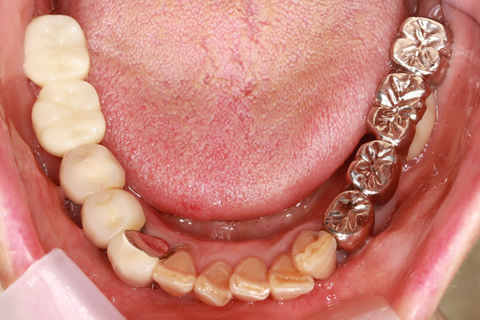

• 症例2

治療前

インプラント埋入時

治療後

年齢・性別

57歳男性

治療期間

3ヶ月

抜歯

なし

治療費

154万円

備考

左上5.6.7 及び左下6.7欠損

治療内容

左上5.6.7と左下6.7欠損部にインプラント埋入

施術の副作用(リスク)

オペによる知覚障害。インプラントによる歯肉炎。インプラント脱落。